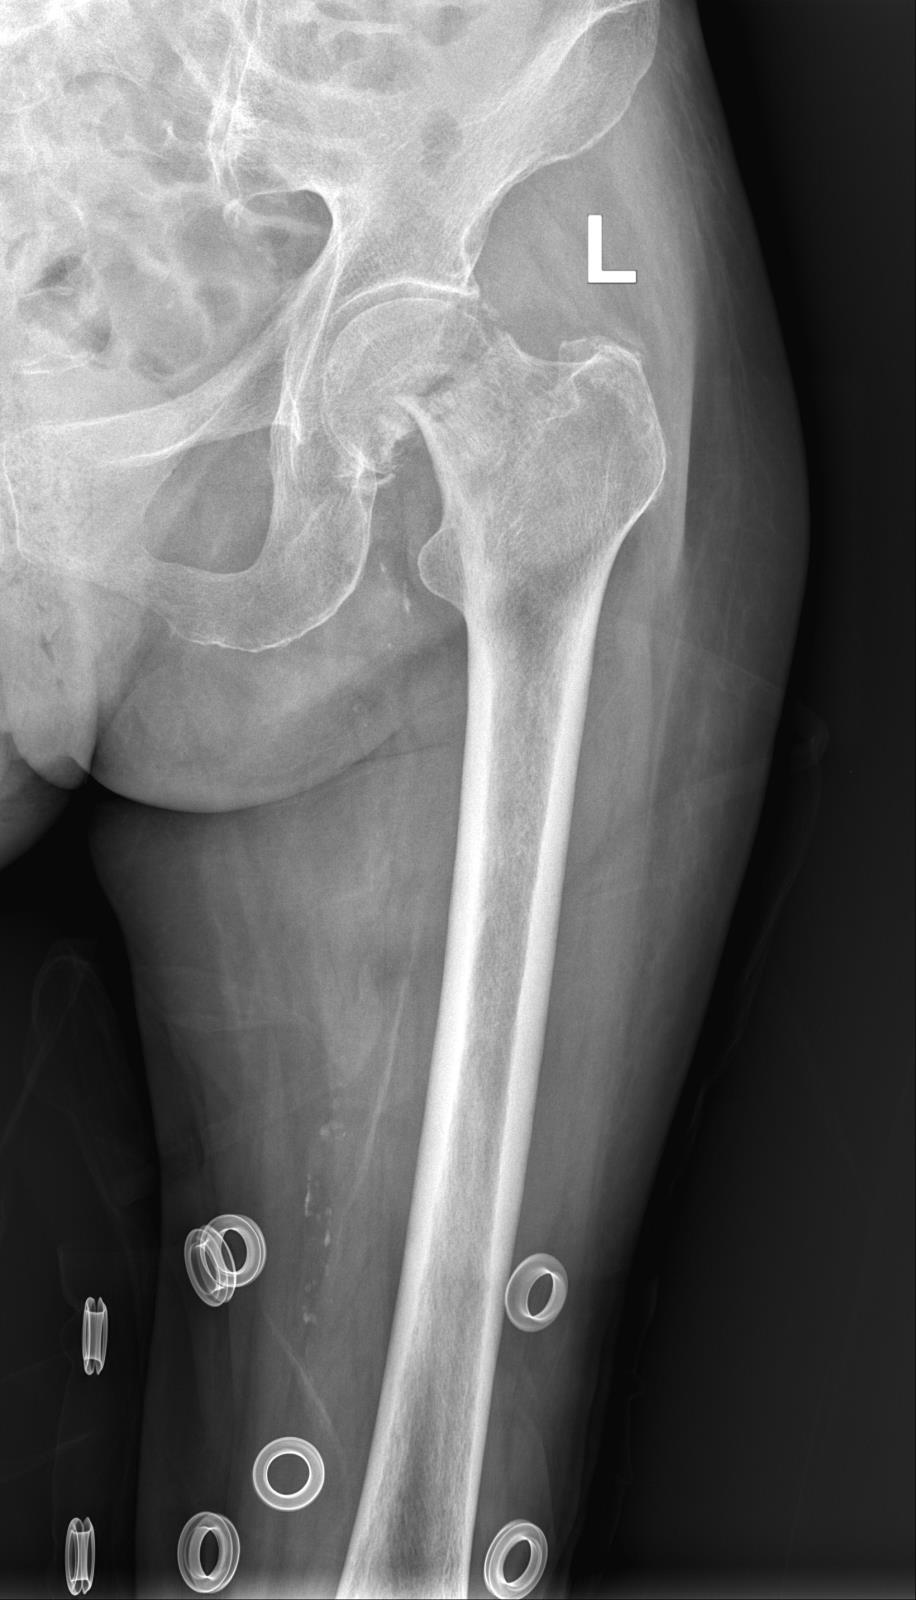

术前DR 术后DR

在严格执行疫情防控要求下,急诊科将患者转运至综合缓冲病房进行治疗,并积极完善相关术前检查,实行三天三检(核酸检测),均为阴性后当天立即转入骨科病房,大外科党委书记、大外科主任、骨科主任肖聪带领科室医疗团队结合患者的各项检查指标结果,进行缜密的病例讨论,与家属商量决定为患者行微创全髋关节置换术。

术前,骨科积极联系相关科室,进行了充分的术前准备,麻醉科指派丰富经验的麻醉师时刻关注患者麻醉期间各项指症数值,全程保驾护航。经过1小时的手术,微创全髋关节置换术成功完成,麻醉完全苏醒后即刻下地行走进行功能锻炼,极大预防了老年患者因卧床导致致命的深静脉血栓、肺部感染、泌尿系统感染等并发症,在专业康复理疗师的指导下进行功能锻炼,目前患者恢复良好,择日即可办理出院。

目前我院骨科已开展微创全髋关节置换日间手术,当天手术麻醉苏醒后立即走出手术室,无痛感,术中出血少,不安置引流管、导尿管、不拆线,手术切口小(仅9cm),当天就可以办理出院,快速回归家庭、社会,极大减轻了患者的经济负担。